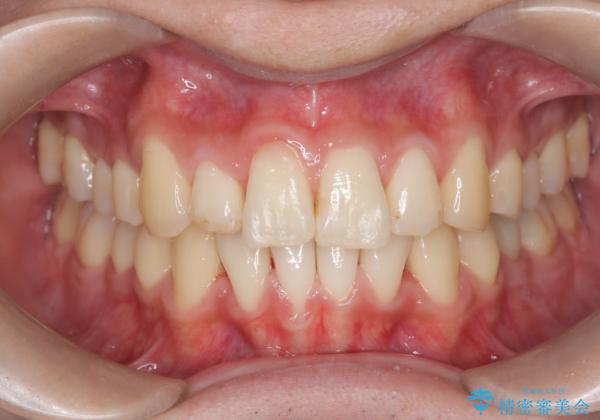

前歯のガタガタを治したい。

- 凸凹を治したいと来院された患者様です。

インビザラインにて、遠心移動を行いながら綺麗に配列することができました。